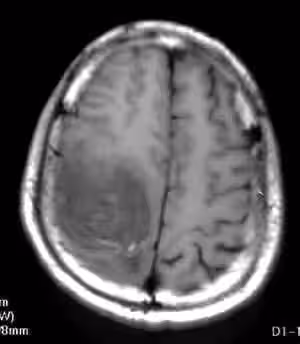

一次例行健康檢查後,醫生告訴何阿嬤,原來,這個寶寶患有重度身心障礙,除腦水腫外,還患有癲癇、過動、斜視等問題。